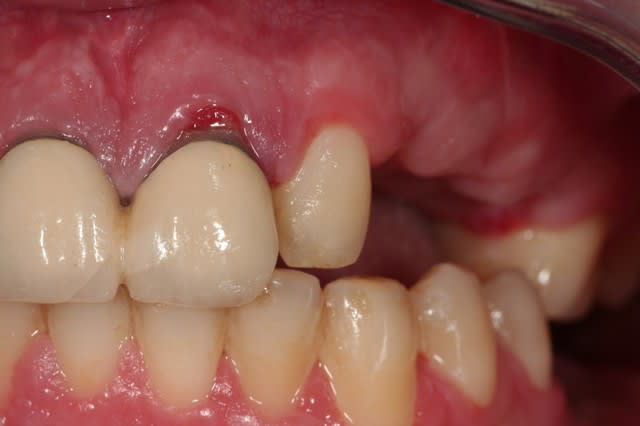

> la 22 est très enfoncée dans son alvéole, elle

> n'est pas fracturée, et silencieuse cliniquement.

> je pensais tricher avec une facette. mais je vais

> avoir un souci de ligne de collet.

si jamais tu decides de garder les laterales,envoie des retros:sur la pano,luxation sur la 12?la 22 intrusee?pas assez clair

les images comme prévu.

son normal à la percussion, à part les cris du patient.

12 cbn0ed - Eugenol

22 llsypc - Eugenol

Si les centrales sont asymptomatiques et de mobilité normale, est-ce que ça ne pourrait pas valoir le coup de tenter de les garder ? Tu ne voudrais pas démonter les couronnes et ré-évaluer notamment la 21 avant de tout dégager ?

La 22 semble fracturée sur la pano, mais c'est peut être un artefact, il faudrait vérifier avec une rétro, mais si c'est le cas, tu es évidemment mal barré pour une traction.

Dans tous les cas, si tu conserves la 22, surveille la pendant quelques mois avec des rétros pour t'assurer de l'absence de résorption.